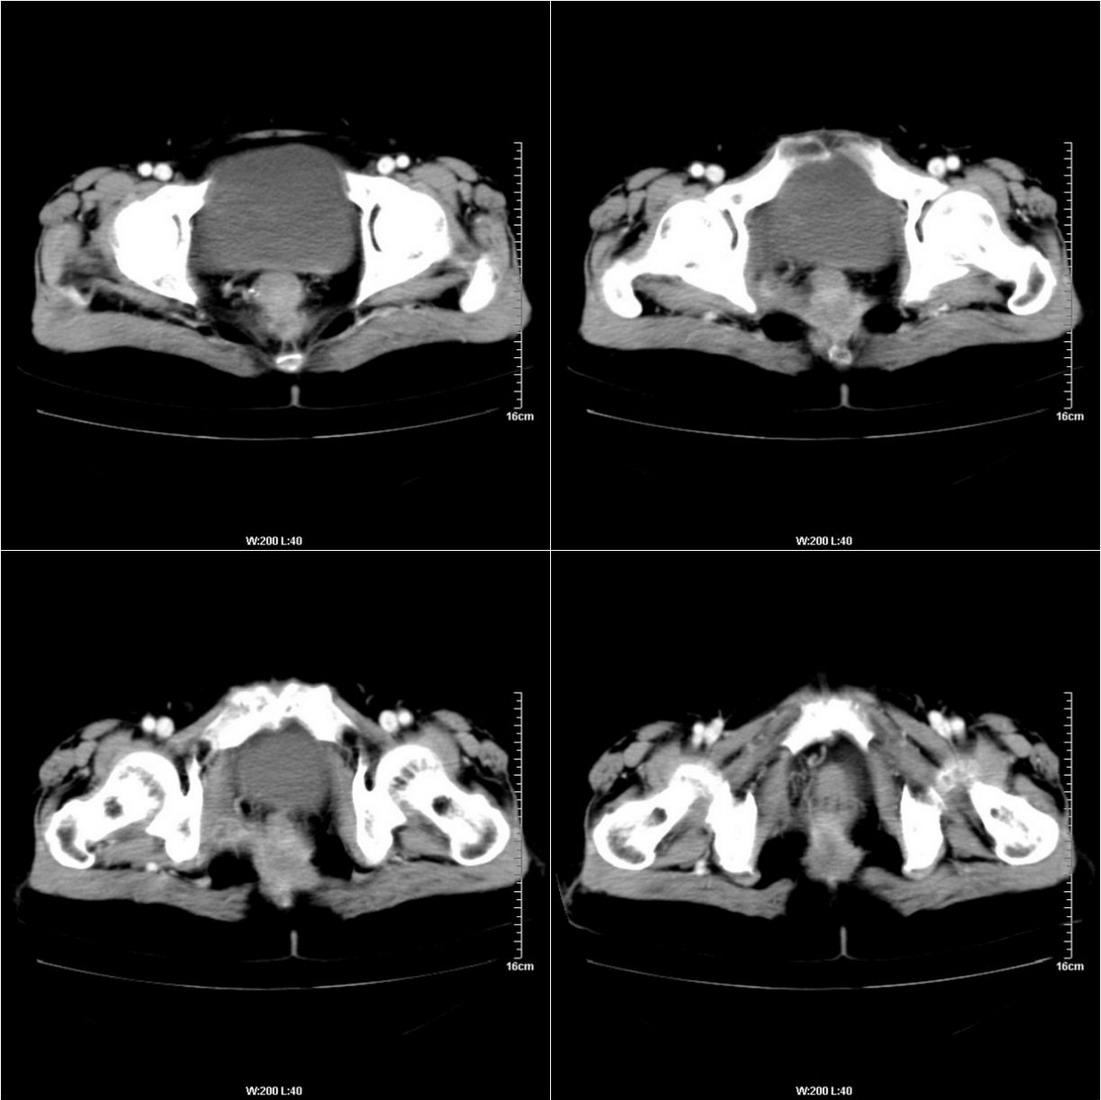

不知道病人的直肠癌手术方式如何,直肠已经全部切除,乙状结肠造瘘于左下腹,肛门应该也没有保留吧?如此,应该是复发了:

病变于肛尾韧带、右侧坐骨肛门窝内并顺右侧肛提肌向右侧闭孔内肌蔓延,骶前软组织内也形成了肿块,麻烦啊!

这个病例还出现了一个有意思的事情:膀胱内在增强的不同时期均有不同形状、位置的高密度出现,并不局限于输尿管开口附近。

是因为尿液中造影剂随输尿管的收缩而排入膀胱内,产生的团片状高密度并进一步弥散而形成的假象吗?渴望哪位老师予以关注并解答,先在此表示感谢了!

膀胱壁见索条状软组织密度影伴强化,可考虑炎性肉芽肿样增生改变,常见于放疗后或慢性感染;直肠及周围软组织见肿块,轻度强化,考虑直肠癌术后复发,并侵犯周围组织